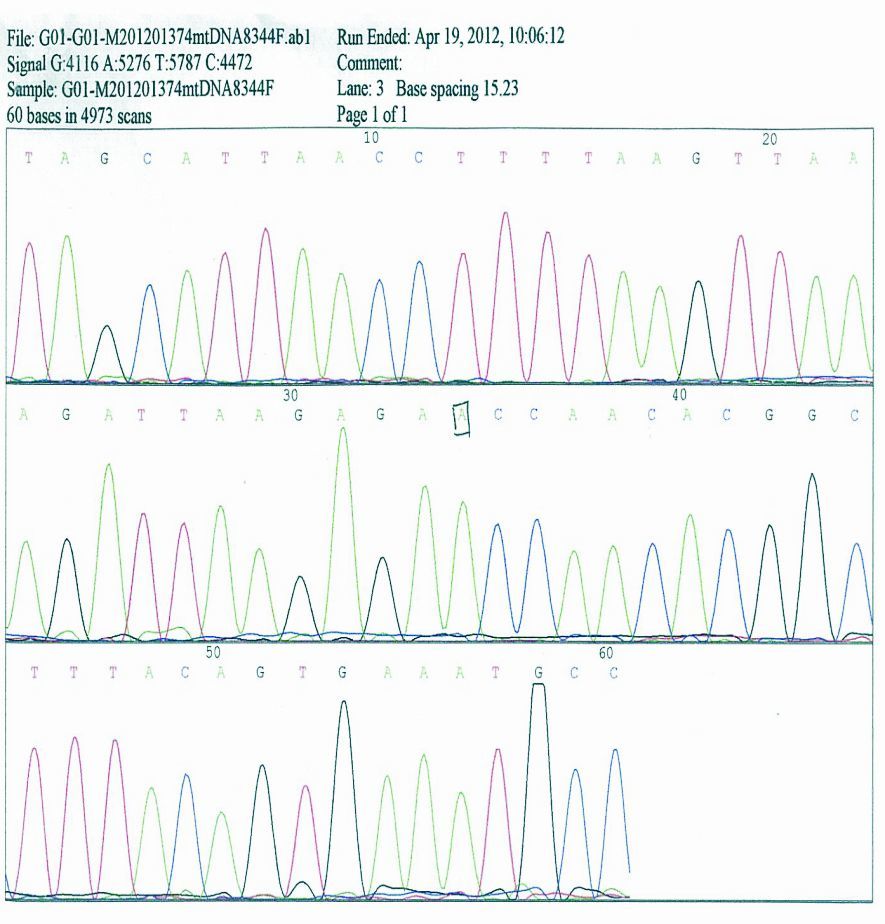

患者杨某,男性,49岁,其母亲有糖尿病病史。于2011年8月15日无明显诱因下出现头痛,以前额为明显,无恶心、呕吐,无双侧眼球一过性黑朦,无二便失禁。当时症状可耐受,未引起注意,同年8月17日家人发现患者反应迟钝、行为异常,言语不能伴有意识模糊,8月18日晨急诊来本院就诊,体温37.6℃,入院途中呕吐一次,非喷射性。急诊行头颅CT检查:左侧额叶稍低密度影。门诊拟“中枢神经系统感染待排”收入院进一步检查、治疗。入院后急诊头颅MRI检查:左侧额叶及皮层下可见片状长T1、T2信号影,轻度脑萎缩,伴脑室扩大,考虑缺血性病变。行脑电图检查:广泛、弥漫性异常改变,可见棘慢波综合、尖慢波综合。心电图为ST-T改变。18日上午10点左右突发意识丧失,面色发绀,牙关紧闭,口吐白沫,口中异常尖叫声,双眼上翻,四肢呈强直性抽搐,头后仰,小便失禁,给予静脉推注地西泮后,症状持续2 min左右抽搐停止,约10 min后神志恢复,对发生事件无记忆。查体:颈软,未见其他阳性神经系统定位体征。给予甘露醇脱水降低颅内压治疗,给予供氧,维持水电解质平衡治疗,考虑中枢神经系统感染引起继发性癫痫发作可能,给予更昔洛韦静脉点滴抗病毒。脑脊液:正常。因患者反复抽搐伴发热,家人要求去外院进一步治疗。外院住院期间诊断糖尿病,经治疗后症状稳定,出院。2012年春节再次抽搐,表现为发热,抽搐,智力明显下降,听觉减退,反应迟钝,消瘦,活动后乏力。相关检查提示线粒体脑病。诱发定位检查:听觉诱发定位(ARB)左侧80 db声强刺激仅引出V波,100 db刺激引出各波各峰间期正常;视觉诱发电位:双侧p1波潜伏期延长;正中神经体感诱发电位(SEP/MD):双侧N3波潜伏期延长,余双侧各波潜伏期正常。考虑左侧听神经功能异常,双侧视觉传导通路功能障碍;双侧正中神经至皮层感觉传导功能障碍。行股四头肌活检:肌膜下或肌纤维内可见不规则红色颗粒状改变称破碎红纤维(RRF)。基因检查(标本:晨尿200 mL,DNA双向测序分析),检查位点 :①线粒体DNA3243;②线粒体DNA8344;检查方法 DNA双向测序分析,该检查中心以NCBI公开发表的基因序列标准序列,将测序结果与其结果对比得出判断,线粒体DNA序列号为NC>012920 。③结果 经序列分析,本例测序所得线粒体DNA第3243位碱基序列与标准序列比较存在mrDNA3243>G基因突变,送检样本检测到线粒体DNA第3243位碱基线粒体脑肌病相关的基因突变,第8344位碱基未检测到与线粒体脑肌病相关的基因突变(见图 1、2)。

| 图 2 第8344位碱基未检测到与线粒体脑肌病相关的基因突变 |